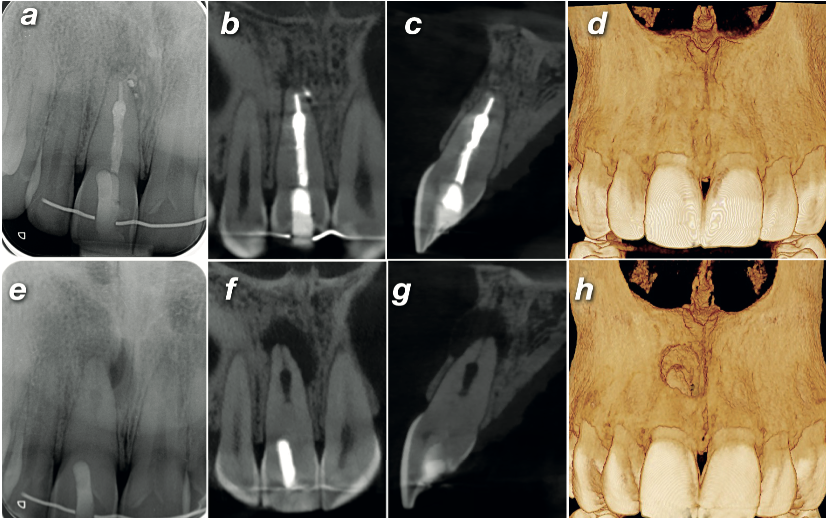

Follow-up radiographs at 1, 3, and 6 months showed no clinical symptoms and a steadily shrinking periapical radiolucency. At 12 months, a follow-up high-resolution CBCT confirmed complete healing of the periapical pathology — and volume rendering showed full regeneration of the buccal cortical plate that had been perforated at the time of diagnosis.

At diagnosis 12-month follow-up

Side-by-side comparison of diagnostic and 12-month follow-up imaging: periapical radiographs, CBCT coronal and sagittal planes, and volume rendering showing complete periapical healing and buccal cortical plate regeneration

Fig. 4 Top row: 12-month follow-up — (a) periapical radiograph showing healed radiolucency, (b–c) CBCT coronal and sagittal planes confirming resolution, (d) volume rendering showing complete buccal cortical plate regeneration. Bottom row: diagnostic imaging for comparison (e–h).